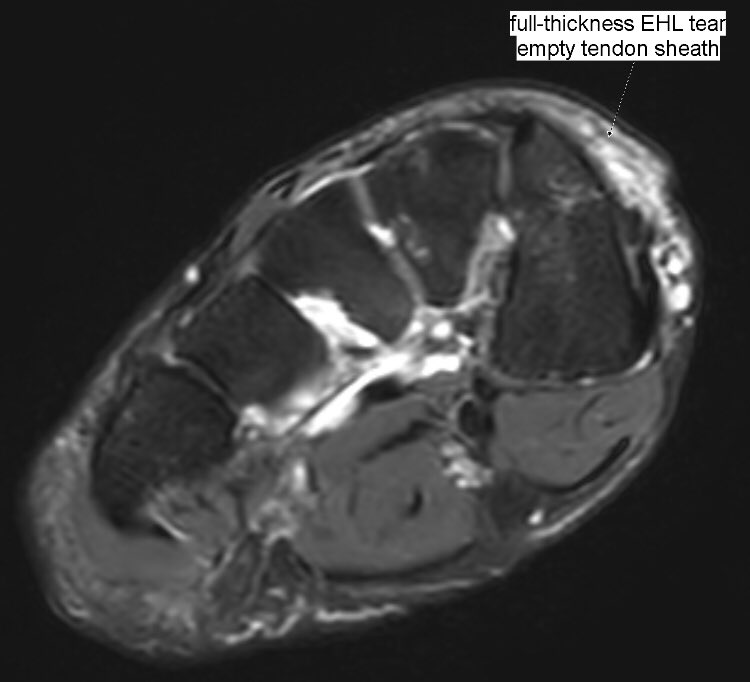

Extensor hallucis longus (EHL) tendon closed full-thickness tear: fluid inside tendon sheath, abrupt EHL tendon fibers complete discontinuity with a 4-cm gap, tendinopathy of both stumps. Mechanical impingement by bone spurs.

#MSKrad#foot#orthopaedicspic.twitter.com/h9LcB2Pgjp